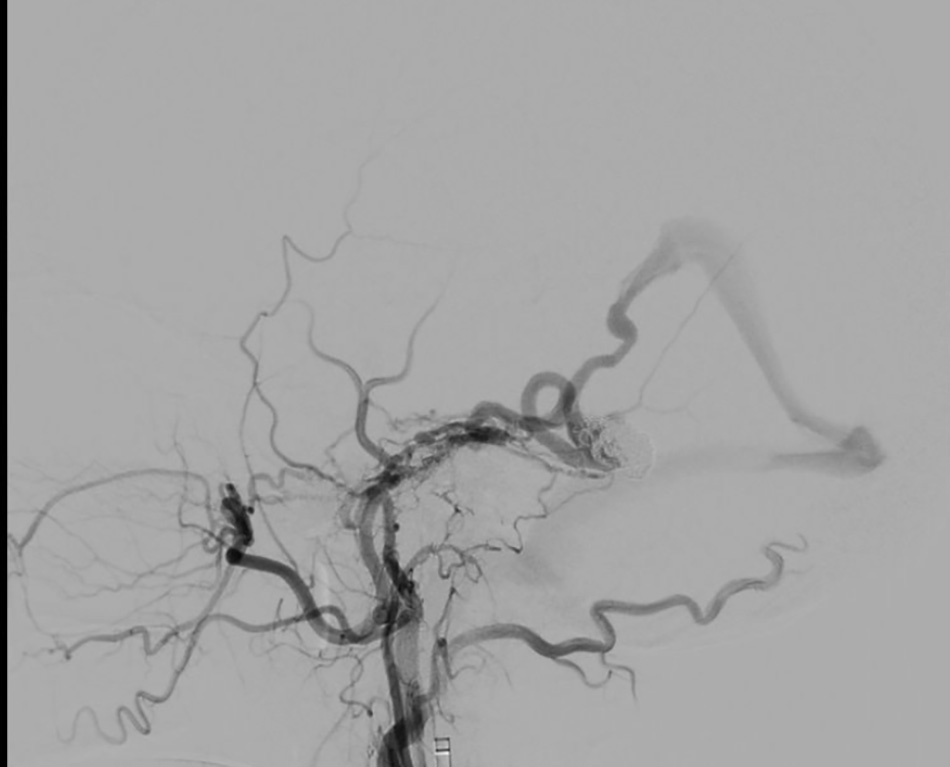

The image shows that the aneurysm has been completely occluded with coils.

Through a small incision in the thigh, Dr Danh carefully guided a catheter and micro-guidewire through the vein to reach the aneurysm in the brain. A total of 12 coils (metallic spiral wires) were placed inside the aneurysm to “patch” the damaged area and block the blood flow through the rupture.